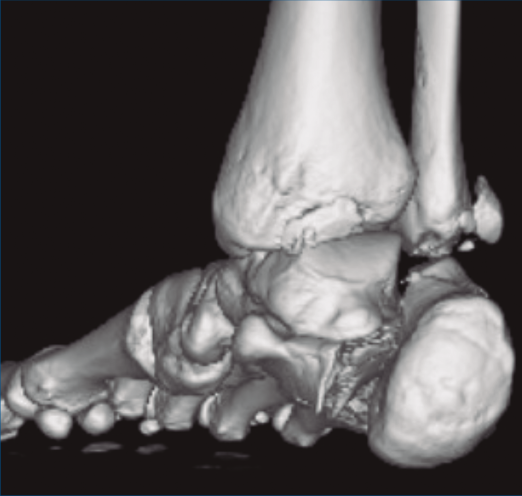

Se trata de un varón de 19 años que ingresa en reanimación tras precipitarse desde una altura de aproximadamente 10 metros. El paciente presenta una fractura estallido de L3 con afectación del canal medular junto con una fractura del vértice inferior de L4, así como una fractura luxación de calcáneo, asociada a una fractura del maléolo peroneo y del maléolo tibial posterior (Figuras 1 a 6) diagnosticadas mediante TC total body (por eso no se dispone de radiografías simples al momento del ingreso). Como podemos comprobar, se trata de una fractura de doble trazo de tipo hundimiento/depresión de la carilla articular (Figuras 5 y 6).

Figura 4. Luxación fragmento posterolateral.

Figura 5. Fractura maléolo peroneo, luxación astrágalo, fractura de doble trazo en calcáneo.

Figura 6. Fractura de doble trazo; se evidencia afectación de la articulación calcaneocuboidea.

A su llegada a urgencias, se inmovilizó con férula posterior de yeso tras no conseguirse la reducción cerrada (Figuras 7 y 8). Debido a la patología asociada, subsidiaria de tratamiento quirúrgico de urgencias (artrodesis de L2 a L4 con tornillos transpediculares, por parte de neurocirugía), se decide demorar eñ tratamiento definitivo de la fractura luxación de calcáneo 2 semanas, hasta conseguir una mejoría en el estado de las partes blandas.